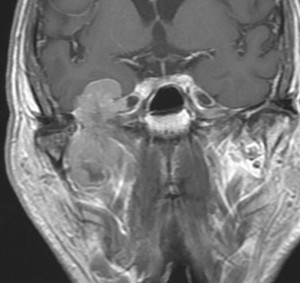

画像と病理所見2

この例は,膠原線維 collagenous tissueのなかに紡錘形の核を有する細胞 spindle cell が見られます。核の大小不同は見られますが,上の例よりはグレードが低いと捉えられます。しかし,この例のように一見グレードが低いと思われる例でも髄液播種や全身転移を生じることがあります。